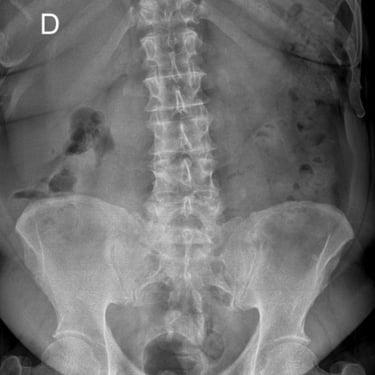

Columna lumbar inestable con listesis: tratamiento con artrodesis y tornillos transpediculares

La listesis lumbar ocurre cuando una vértebra se desplaza hacia adelante o hacia atrás respecto a la vértebra inferior, generando inestabilidad de la columna lumbar. Esta condición puede causar dolor lumbar crónico, compresión nerviosa, ciática, debilidad en las piernas o dificultad para caminar. Cuando el tratamiento conservador no es suficiente, la artrodesis lumbar con tornillos transpediculares es una alternativa quirúrgica eficaz. Este procedimiento permite fijar las vértebras afectadas mediante implantes que estabilizan la columna y favorecen la fusión ósea. Con técnicas modernas y abordajes mínimamente invasivos, se logra aliviar el dolor, mejorar la estabilidad vertebral y recuperar la función del paciente.